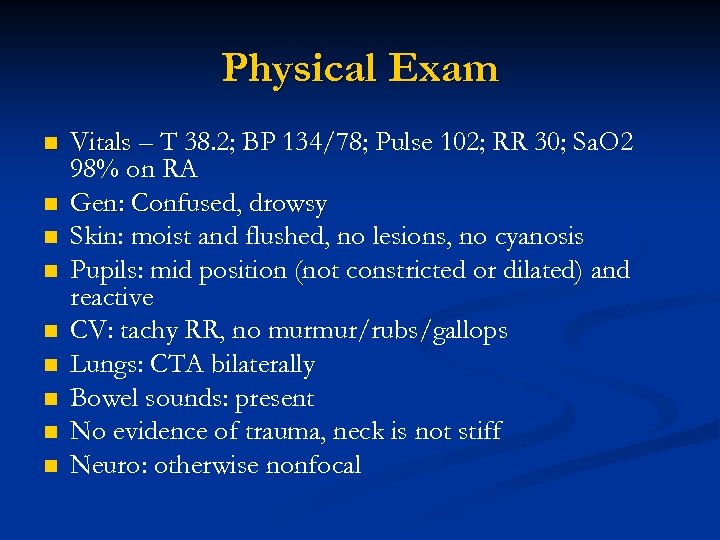

Physical Exam n n n n n Vitals – T 38. 2; BP 134/78; Pulse 102; RR 30; Sa. O 2 98% on RA Gen: Confused, drowsy Skin: moist and flushed, no lesions, no cyanosis Pupils: mid position (not constricted or dilated) and reactive CV: tachy RR, no murmur/rubs/gallops Lungs: CTA bilaterally Bowel sounds: present No evidence of trauma, neck is not stiff Neuro: otherwise nonfocal

Physical Exam n n n n n Vitals – T 38. 2; BP 134/78; Pulse 102; RR 30; Sa. O 2 98% on RA Gen: Confused, drowsy Skin: moist and flushed, no lesions, no cyanosis Pupils: mid position (not constricted or dilated) and reactive CV: tachy RR, no murmur/rubs/gallops Lungs: CTA bilaterally Bowel sounds: present No evidence of trauma, neck is not stiff Neuro: otherwise nonfocal